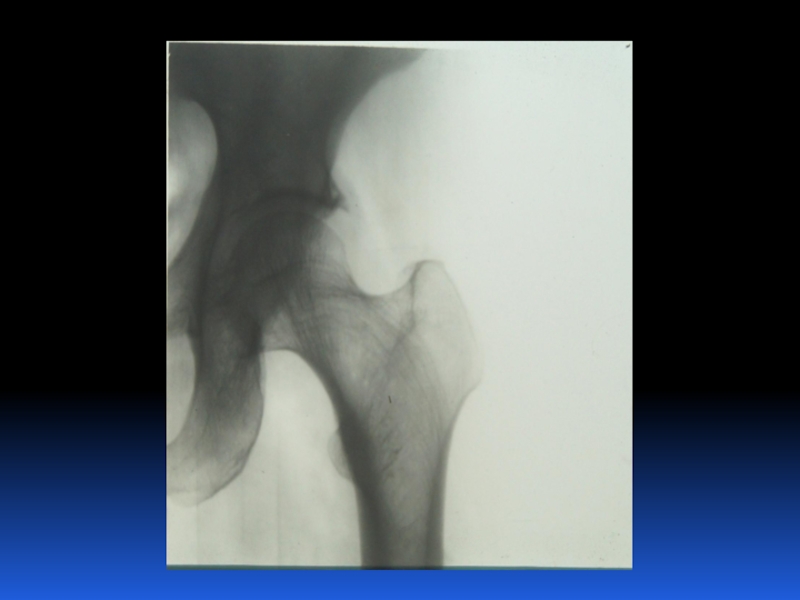

Остеопороз – это системное заболевание скелета, характеризующееся снижением костной массы и нарушением микроархитектоники костной ткани, с последующим увеличением хрупкости костей, со склонностью к патологическим переломам.

Слайд 2 Остеопороз – это системное заболевание скелета, характеризующееся снижением костной

массы и нарушением микроархитектоники костной ткани, с последующим увеличением хрупкости

костей, со склонностью к патологическим переломам.